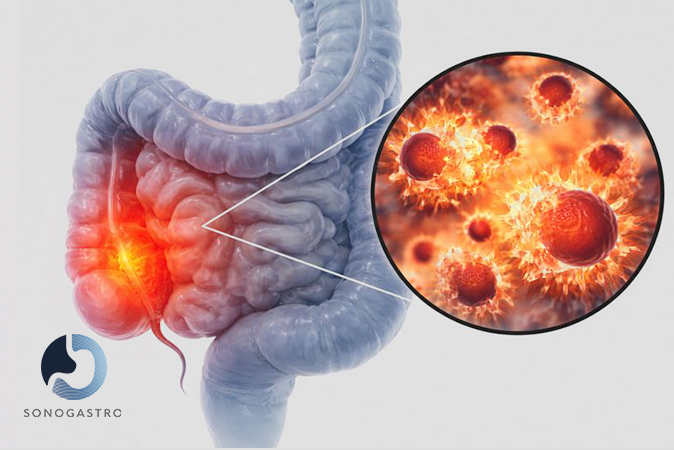

Colonoscopy evaluation and prevention.

Lower Digestive Conditions

Irritable bowel syndrome (IBS)

Diverticulosis/Diverticulitis

Acute or chronic constipation

Abdominal bloating and gas

Inflammatory bowel disease (Crohn’s, ulcerative colitis)

Polyps

Hemorrhoids, Anal Fissures, & Fistulas

Malabsorption Syndromes